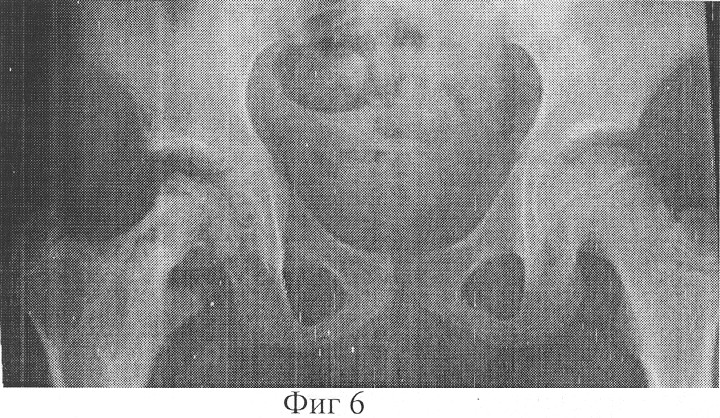

Фиг.6 – копия рентгенограммы пациентки после фиксации вертельной области, зоны удлинения, шейки и головки бедра спицами;

Больной проведено оперативное вмешательство. В операционной под внутривенным наркозом через крыло подвздошной кости проведено 4 спицы, которые фиксированы в дуге и натянуты. Через дистальный метафиз бедра проведено 3 спицы, которые фиксированы в 3/4 кольца и натянуты. На границе верхней трети и средней трети бедра в сагиттальной плоскости проведены две перекрещивающиеся спицы с упорными площадками, фиксированы в дуге, которая соединена с опорой на дистальном метафизе бедра с помощью стержней. Бедро установлено в положение отведения 30°, разгибания 180° и внутренней ротации 40°. Через дистальный отдел шейки в сагиттальной плоскости проведены две перекрещивающиеся под углом 15° спицы с упорными площадками навстречу друг другу, которые фиксированы в дуговой опоре и натянуты. Опору соединили с дугой на подвздошной кости стержнями Через разрез 4 см по передней поверхности бедра в вертельной области произведена С-образную остеотомия бедра от верхне-наружнего края шейки до верхнего края малого вертела. Дистальный отдел бедренной кости приведен на 30° и ротирован внутрь на 25°. Опоры, установленные на шейке бедра и на границе верхней и средней трети бедра соединены стержнями с шарнирными устройствами. Стержни установлены в направлении сверху вниз изнутри кнаружи перпендикулярно линии, касательной к плоскости входа во впадину. Наложены швы на рану. С шестого дня в течение 48 суток производили дистракцию в зоне остеотомии 0,5 мм в сутки (Фиг.4). После окончания дистракции в операционной под наркозом через через вертельную область, зону удлинения, шейку и головку бедра проведены 6 спиц, свободные концы которых фиксированы к опоре, расположенной на границе верхней трети и средней трети бедра (Фиг.5). Удалены спицы, проходившие через шейку бедренной кости. Продолжительность фиксации фрагментов бедренной кости в корригированном состоянии 90 дней. После демонтажа аппарата и удаления спиц проведен курс восстановительного лечения.

Через 10 месяцев после снятия аппарата пациентка ходит с умеренной нагрузкой на правую ногу. Относительная длина нижних конечностей одинаковая. Амплитуда движений в правом тазобедренном суставе восстановилась полностью. По данным рентгенографии: головка правого бедра центрирована во впадине, степень покрытия ее крышей впадины 100%, угол Виберга 20°, шеечно-диафизарный угол составляет 120°, угол антеверзии 15°.